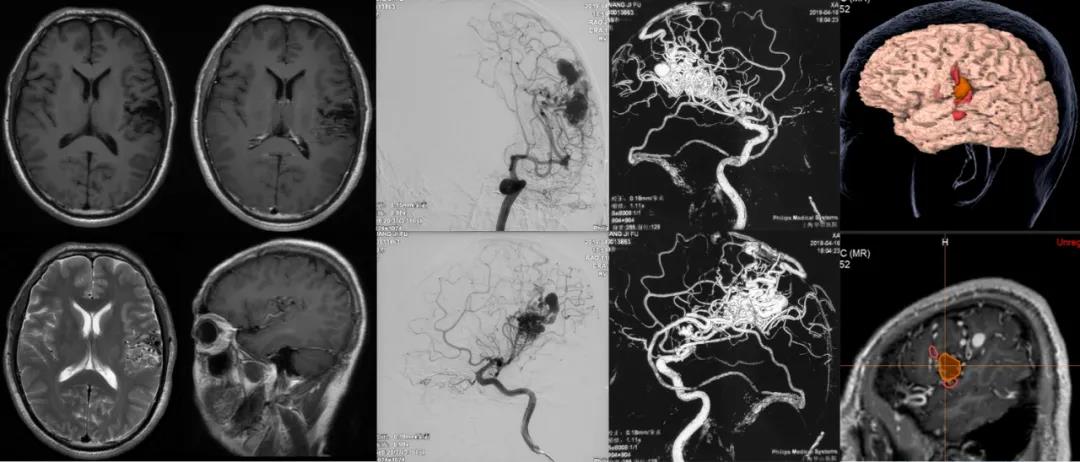

病例简介:

患者,男性, 58岁

主诉: 9个月前体检发现颅内病灶.

既往史: 无特殊

体格检查: 神经系统检查无明显异常

术前影像资料:

术后影像资料:

患者术后恢复情况:

一般状况良好,四肢肌力无影响,术后2周内有部分运动性失语,现已恢复。